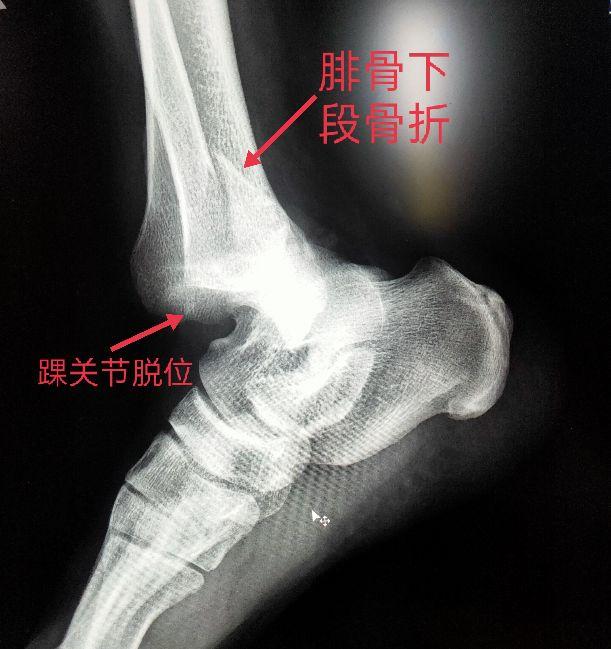

四、踝关节部位的骨折、脱位X线片

车祸、摔跤、跌倒都会造成骨折或脱位。以踝部、距骨、跟骨多见。

脚踝是哪个部位图解,脚踝是哪个部位图解视频(学习《X线读片指南》骨、关节系统——踝关节)